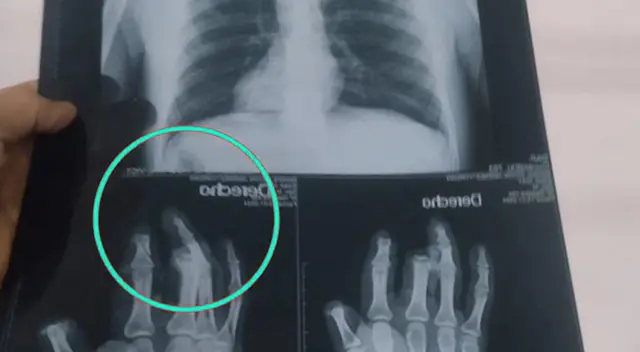

En una situación insólita en la región de Huánuco, un hombre sufrió graves heridas tras la detonación de un explosivo en su mano derecha, provocando la pérdida de varios dedos.

La víctima, identificada como Yordan Aquilino, se encuentra bajo investigación policial junto a su presunto cómplice, Ítalo Domínguez, por su presunta participación en un caso de extorsión.

Según información de las autoridades, la conexión entre Aquilino y las llamadas extorsivas dirigidas a un empresario del sector gastronómico fue descubierta por la fiscal Ingrid Osorio Cadillo.

El impactante incidente revela un giro inesperado en la investigación de este presunto delito. Con el historial delictivo de los involucrados en consideración, la Policía procedió a la detención de Aquilino y Domínguez.

El juez César Villanueva ha dictaminado una detención preliminar de siete días para ambos, extendiéndose hasta el 19 de enero, mientras avanzan las indagaciones.